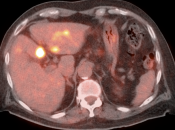

• The utility of PET/CT lies in its assessment of regional nodes and distant metastatic disease.

• Distant Disease: Most commonly to the liver, peritoneum, lung and bone.

Assessing Response to Therapy & Prognosis:

• Early Response: Non-responders can be offered alternative therapy.

• Late Response: Assess success or failure of therapy, and ultimate outcome.